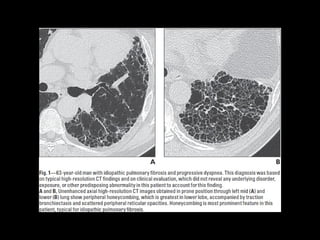

UIP TC

• Fibrosis con áreas normales.

• Disminución de volumen pulmonar

• Opacidades reticulares

• Vidrio esmerilado

• Predominio en regiones basales y subpleurales

• Distorsión arquitectónica con bronquiectasias por tracción

secundaria a fibrosis.

• Panal de abejas (2-20mm)

• Linfoadenopatías mediastínicas pequeñas.

UIP TC • Fibrosiscon áreas normales. • Disminución de volumen pulmonar • Opacidades reticulares • Vidrio esmerilado • Predominio en regiones basales y subpleurales • Distorsión arquitectónica con bronquiectasias por tracción secundaria a fibrosis. • Panal de abejas (2-20mm) • Linfoadenopatías mediastínicas pequeñas.